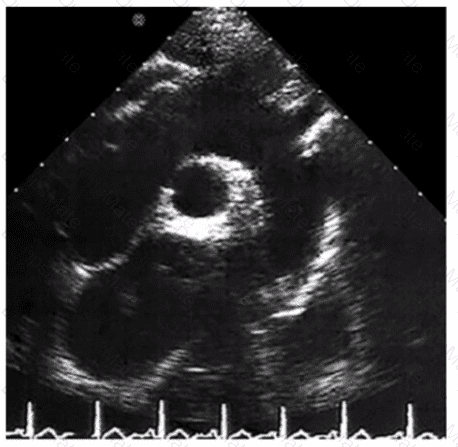

Which pathology is consistent with the left ventricular strain pattern shown in this image?

AE-Adult-Echocardiography Question 5

Options:

A.

Amyloidosis

B.

Apical hypertrophy

C.

Non-ischemic cardiomyopathy

D.

Right coronary artery infarct